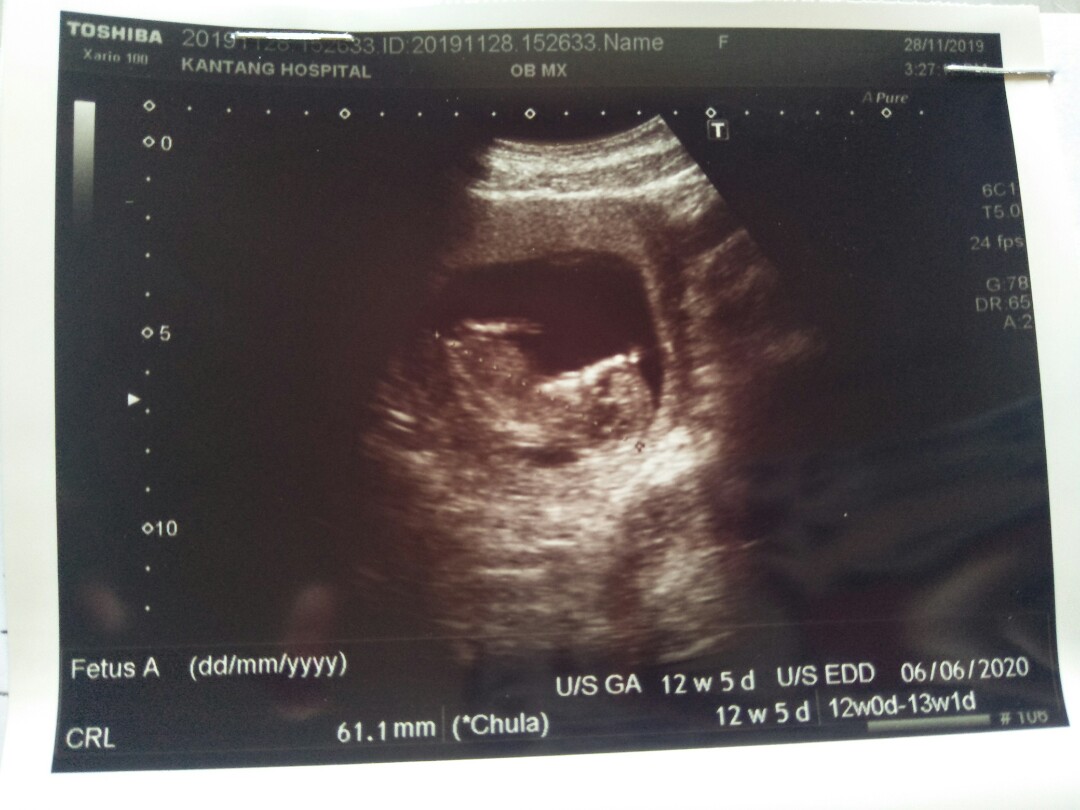

มีภาพตอน12w+5d ค่ะ